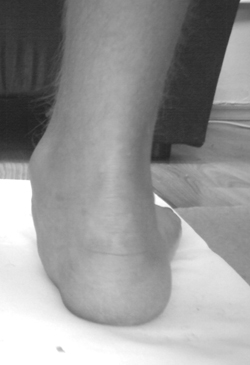

Рентгенологический метод использовался в качестве подтверждающего и определял вид продольного плоскостопия. Выполнялись рентгенограммы обеих стоп в дорсоплантар-ной и латеральной проекциях в положении стоя. По рентгенограммам измерялись следующее показатели: угол продольного свода стопы, угол наклона пяточной кости, таран-но-I-плюсневый угол (ТПлУ), таранно-пяточный угол (ТПУ), кубовидно-пяточный угол (КПУ) и высота свода. Также проводилась рентгенометрия переднего отдела стопы если имелось поперечное плоскостопие. Для выявления распределения нагрузки на стопу использовалась плантография. Всех больных оценивали перед операцией по шкале Американского ортопедического общества стопы и голеностопного сустава (AOFAS) [8].

|

| Рисунок 6. Рентгенограмма после операции, боковая проекция |

Баллы оценивались по шкале AOFAS, и существенно улучшились от значения в 47,2 до операции, до среднего значения 79,0 при последующем обследовании. Если провести анализ различных параметров, оцениваемых по этой шкале, можно заключить, что в среднем улучшение по болям произошло от 16,3 до 30,0, улучшение функций стопы и пятки при среднем значении до операции 28,7 достигло после операции величины 41,6, а правильное положение изменилось от среднего значения 2,6 до величины 8,4 при последующем обследовании (рис. 7,8). Рентгеновские снимки показали среднее уменьшение угла продольного свода в 14,3о и среднее уменьшение угла отклонения ТС между таранной и пяточной костью на 8о.